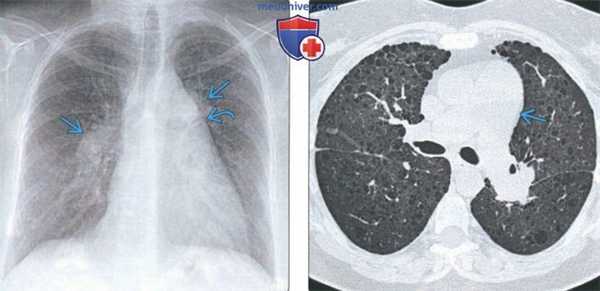

(Слева) На рентгенограмме органов грудной клетки в прямой проекции у пациента с эмфиземой легких и легочной гипертензией определяется расширение центральных легочных артерий. Дугообразное выбухание левого контура верхнего средостениям соотносится с расширением легочного ствола.

(Справа) На аксиальной КТВР у этого же пациента определяется центрилобулярная эмфизема и расширение легочного ствола. Хроническое обструктивное заболевание легких и интерстициальное заболевание легких в конечном счете приводят к возникновению легочной гипертензии.